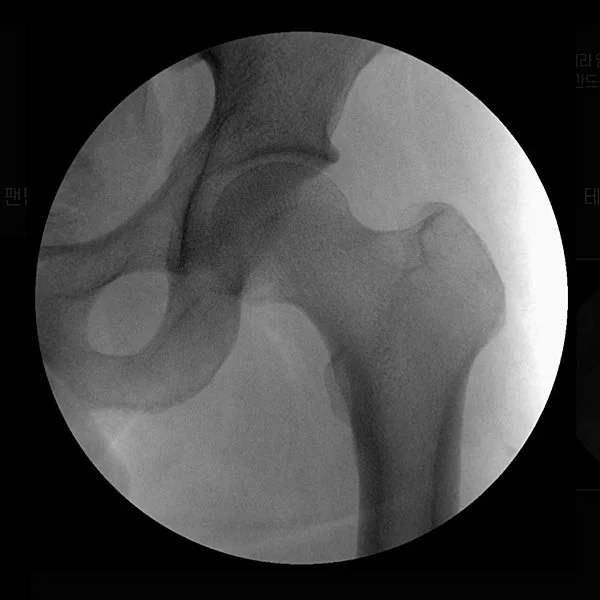

Take 23. Hip Joint without Filter

Take 23. Hip Joint with Filter